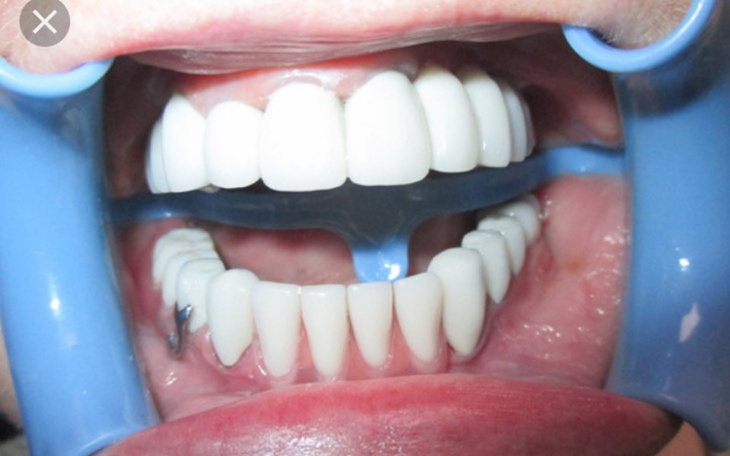

(Na zdjęciach widać brak już jednego zęba (7). Kanały nie są dostatecznie wypełnione do końca.)